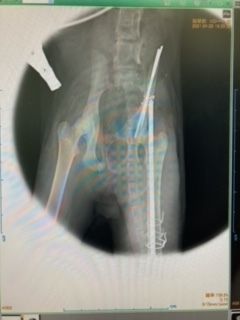

骨盤と左大腿骨の2箇所を骨折しており、すぐにでも手術が必要な状態でした。

骨盤骨折(左写真)で当初肛門が圧迫され狭まっており、便排出が

出来ない恐れもあり、それを広げる手術が必要になる可能性もありました。

4/28 金属プレートで骨を固定する手術をしました。幸いにも排便に支障がある程の状況迄至らず無事に手術は成功しそのまま安静の為入院となりました。

現在自宅に一旦引き取り安静にしています。後日再度金属ボルトを取り出す手術を控えています。左写真では足が動かせないからか野良猫だからかトイレを定位置としています。この保護当時は目が合えばシャーっと威嚇をして慣れてくれるまで時間がかかりそうでした。

・治療・手術内容:骨盤、左大腿骨骨折によるボルト固定手術・入院・抜糸・完治後ボルト摘出

骨盤と左足骨折の手術